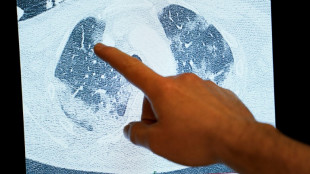

China no detectó patógenos "inusuales o nuevos" relacionados con repunte de enfermedades respiratorias

China no detectó patógenos "inusuales o nuevos" relacionados con un repunte de enfermedades respiratorias en el norte del país, afirmó este jueves la Organización Mundial de la Salud (OMS).

La OMS pide a China información sobre un repunte de las enfermedades respiratorias

La Organización Mundial de la Salud (OMS) ha pedido información adicional a China sobre un repunte de enfermedades respiratorias en el norte del país, una solicitud que Pekín no comentó de momento públicamente.